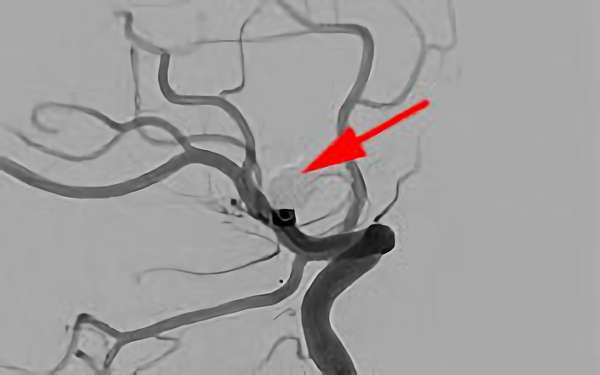

No.1631 手術前